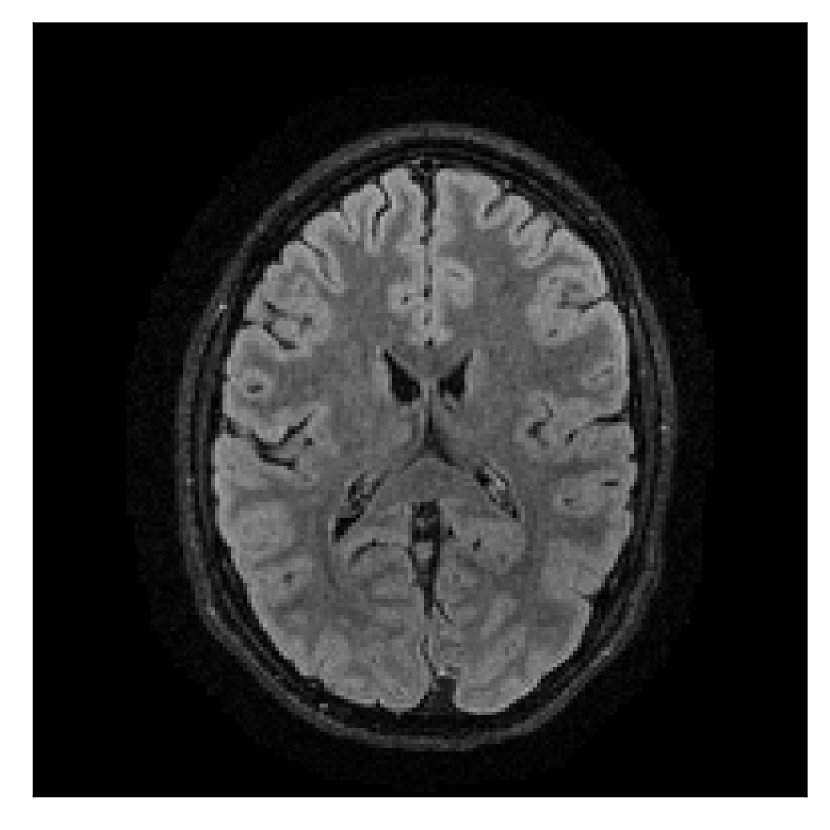

We consider three levels of motion corruption: (i) the volunteer moves once, (ii) the volunteer moves twice, and (iii) the volunteer moves five times. The volunteer is instructed to change its head position every time it is prompted to do so, and maintain that position in between instructions. We use T2-FLAIR-weighted contrasts as corrupted scans, with T1-weighted contrast as a reference (see Table 1 for further details). The corrupted acquisition employs randomized sampling.

4.1 Experiment 1: robustness test

We gather the results for the robustness test described in Section 3.1 (volunteer 1) in Figures 2, 4, and 6 for motion corruption mechanisms associated to one, two, and five changes of position, respectively. Furthermore, we juxtapose the corrected images with varying degrees of corruption in Figure 8. We observe that the proposed method consistently ameliorates the corrupted scan. The quality indexes based on PSNR and SSIM show only a modest decrease in correction quality as a function of motion complexity (Figure 8).

| Section 3.1, Figure 2 | Sagittal | 23.94 | 27.95 | 0.7068 | 0.7936 |

| Coronal | 26.66 | 29.82 | 0.7653 | 0.8332 | |

| Axial | 25.40 | 30.16 | 0.7616 | 0.8490 | |

| Section 3.1, Figure 2 | T2-FLAIR | Completely corrected | Some blurring | No additional artifacts | Good grey white matter differentiation |